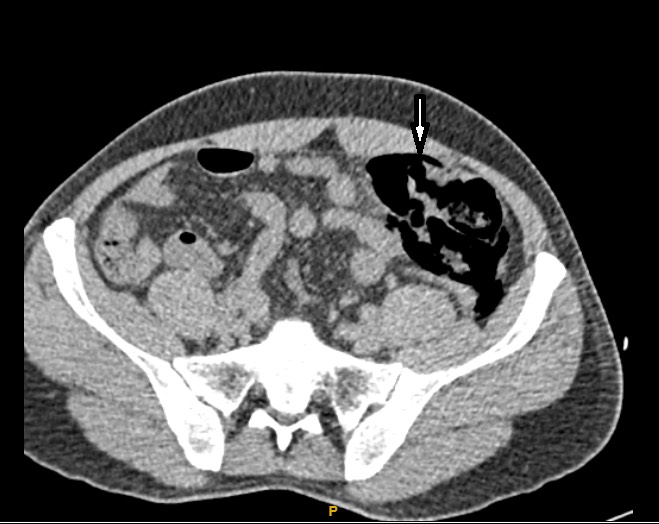

Với hình ảnh này chúng tôi nghĩ đến 2 khả năng: viêm túi thừa đại tràng xích ma hoặc vỡ đại tràng xích ma dưới thanh mạc. Tuy nhiên đau khởi phát sau một chấn thương bụng kín nên khả năng vỡ đại tràng dưới thanh mạc được ưu tiên và tìm cách để xác minh. Bênh nhân được đặt thông hậu môn và bơm khoảng 500 ml khí sau đó kẹp thông và chụp lại phim CT scanner. Kết quả phim CT scanner lần này bóng hơi cạnh đại tràng sigma trên phim trước to ra kèm có hơi tự do ổ phúc mạc (Hình 3 và 4). Chẩn đoán vỡ đại tràng sigma được xác định và bệnh nhân được mổ cấp cứu. Trong mổ phát hiện đai tràng sigma vỡ dưới thanh mạc ở bờ tự do, kích thước khoảng 1 cm, bờ lỗ vỡ bình thường, không có dấu hiệu của túi thừa đại tràng. ổ bụng sạch, có ít dịch xuất tiết (Hình 5). Lỗ vỡ được đóng ngay thì đầu bằng vicril 2.0 hai lớp khâu vắt. Quá trình hậu phẫu bình thường, bệnh nhân được xuất viện sau 7 ngày, không có biến chứng sau mổ .

Hình 3

Hình 4

Bóng hơi cạnh đại tràng to ra và chỗ vỡ đại tràng sau bơm hơi

Trong trường hợp của chúng tôi, đại tràng sigma chỉ vỡ lớp niêm mạc và cơ. Phân và hơi thoát khỏi lòng ruột bị phúc mạc tạng giữ lại, nó làm căng và kích thích phúc mạc tạng gây đau bụng liên tục. Tuy nhiên đau ở đây chỉ khu trú một vùng bụng, không lan rộng giữa 2 lần khám bệnh. Hơi và phân khu trú tại chỗ dưới thanh mạc nên các phương tiện chẩn đoán hình ảnh như x quang bụng đứng, siêu âm hay thậm chí là CT scanner để tìm hơi tự do ổ phúc mạc đều bó tay. Với triệu chứng đau liên tục, dai dẳng, không đáp ứng với các thuốc giảm đau thông thường nhưng cũng không lan rộng sau các lần khám kèm theo dấu hiệu bạch cầu máu tăng nhẹ khiến chúng tôi không thể loại trừ khả năng bệnh nhân bị vỡ tạng rỗng sau chấn thương. May mắn thay trên phim CT scanner chúng tôi thấy có hình ảnh thâm nhiễm viêm kèm bóng hơi  khu trú cạnh đại tràng sigma. Trong hoàn cảnh chấn thương bụng kín thì khả năng vỡ đại tràng dưới thanh mạc là rất lớn. Nếu không được can thiệp thì theo tiến triển của bệnh lớp thanh mạc này sẽ hoại tử theo thời gian và thủng gây viêm phúc mạc làm tăng tỷ lệ biến chứng và tử vong có thể xảy ra trong thời kỳ hạu phẫu.  Chính vì vậy phải nhanh chóng tìm cách làm rõ chẩn đoán. Chúng tôi đã chọn cách bơm hơi đại tràng rồi chụp CT scanner lại để tìm dấu hiệu hơi tự do trong ổ phúc mạc. Quả thực sau khi bơm 500 ml hơi qua thông hậu môn rồi chụp CT scanner lại chúng tôi đã tìm được hơi tự do ổ phúc mạc, bóng hơi cạnh đại tràng sigma tăng lên và thậm chí thấy cả chỗ vỡ trên thành đại tràng.